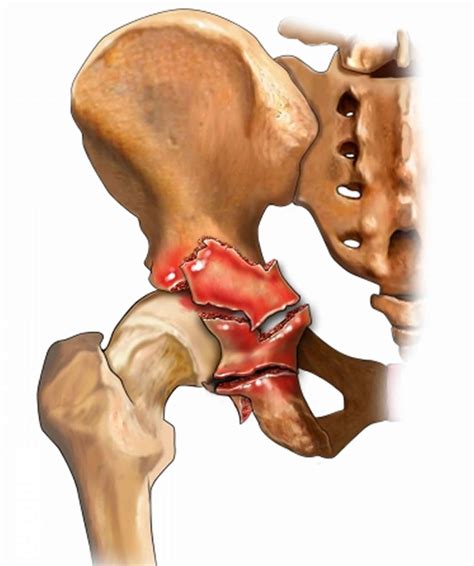

Fractures of the acetabulum are complex injuries that involve the socket portion of the hip joint. These fractures can result from high-energy trauma, such as motor vehicle accidents or falls from significant heights. The acetabulum is a critical component of the hip joint, providing stability and support for the femoral head. Understanding the types, causes, diagnosis, and treatment options for fractures of the acetabulum is essential for healthcare professionals and patients alike.

The acetabulum is a cup-shaped socket in the pelvis that articulates with the femoral head to form the hip joint. It is composed of the ilium, ischium, and pubis bones, which fuse together during development. The acetabulum provides a stable and secure environment for the femoral head, allowing for a wide range of motion while maintaining joint integrity.

Classification of Fractures of the Acetabulum

Fractures of the acetabulum are classified based on the pattern and location of the fracture. The most commonly used classification system is the Letournel and Judet classification, which categorizes acetabular fractures into ten distinct types:

Type Description

Posterior Wall Fracture of the posterior wall of the acetabulum

Posterior Column Fracture of the posterior column of the acetabulum

Anterior Wall Fracture of the anterior wall of the acetabulum

Anterior Column Fracture of the anterior column of the acetabulum

Transverse Horizontal fracture line across the acetabulum

T-shaped Transverse fracture with a vertical component

Posterior Column and Posterior Wall Combined fracture of the posterior column and wall

Anterior Column and Posterior Hemi-Transverse Combined fracture of the anterior column and posterior hemi-transverse

Both Columns Fracture involving both the anterior and posterior columns